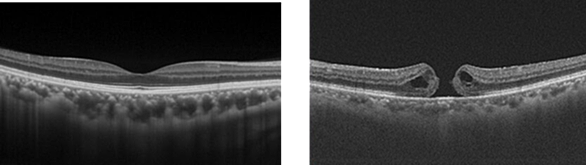

網膜の央部で光を認識し、視覚反応につなげる最も重要な部位が黄斑。この部位が発症すると、ものが歪みや二重に見える現象等の視覚障害、失明のリスクを生ずる。

黄斑変性は、視覚細胞の脂質部分の酸化劣化により、細胞内への酸素等の栄養素の搬入経路が機能しなくなった為に、視覚細胞が壊死して生ずる説が一般的で、目に限らない一般的な活性酸素による健康障害と同じ理屈で発症前の予防、発症後の治療が論じられる。